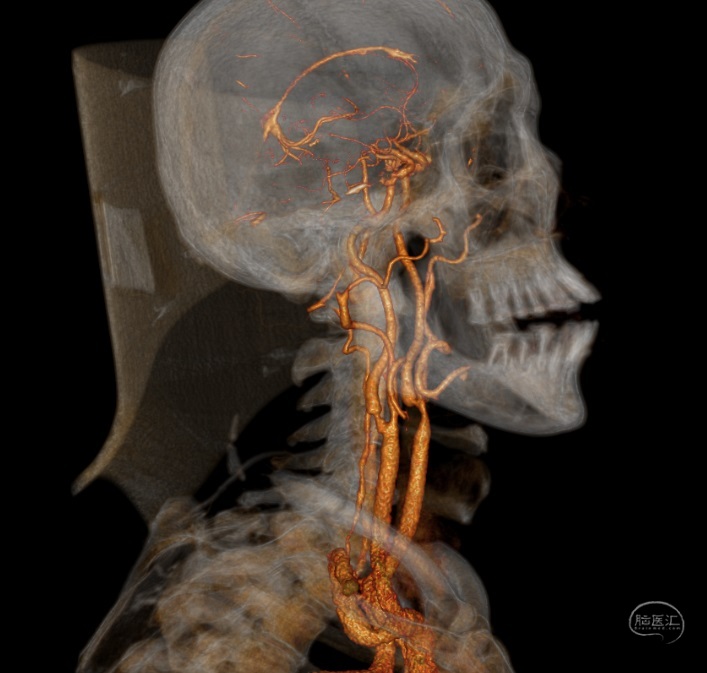

患者李XX,男性,63岁,主因右肢无力1月入院

既往高血压病史,糖尿病史,脑梗死病史5年,遗留优质活动不利,冠心病病史

查体:BP:129/75mmHg,神情,言语正确,四肢从嘱,GCS:15分,双侧瞳孔各3mm,对光反射灵敏,右侧肌力4级,左侧5级

颈动脉内膜剥脱术

患者李XX,男性,63岁,主因右肢无力1月入院

既往高血压病史,糖尿病史,脑梗死病史5年,遗留优质活动不利,冠心病病史

查体:BP:129/75mmHg,神情,言语正确,四肢从嘱,GCS:15分,双侧瞳孔各3mm,对光反射灵敏,右侧肌力4级,左侧5级